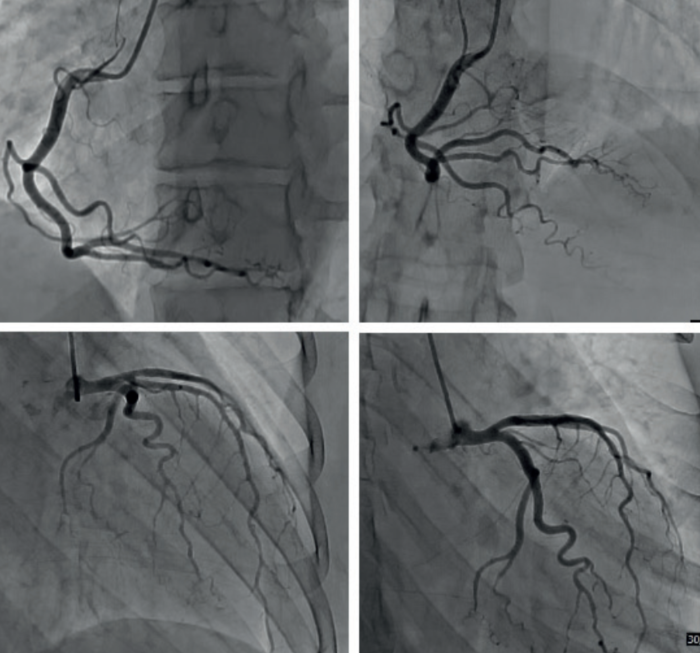

Se realizó cineangiocoronariografía (CACG) que mostró arterias coronarias epicárdicas sin lesiones angiográficamente significativas (figura 3).